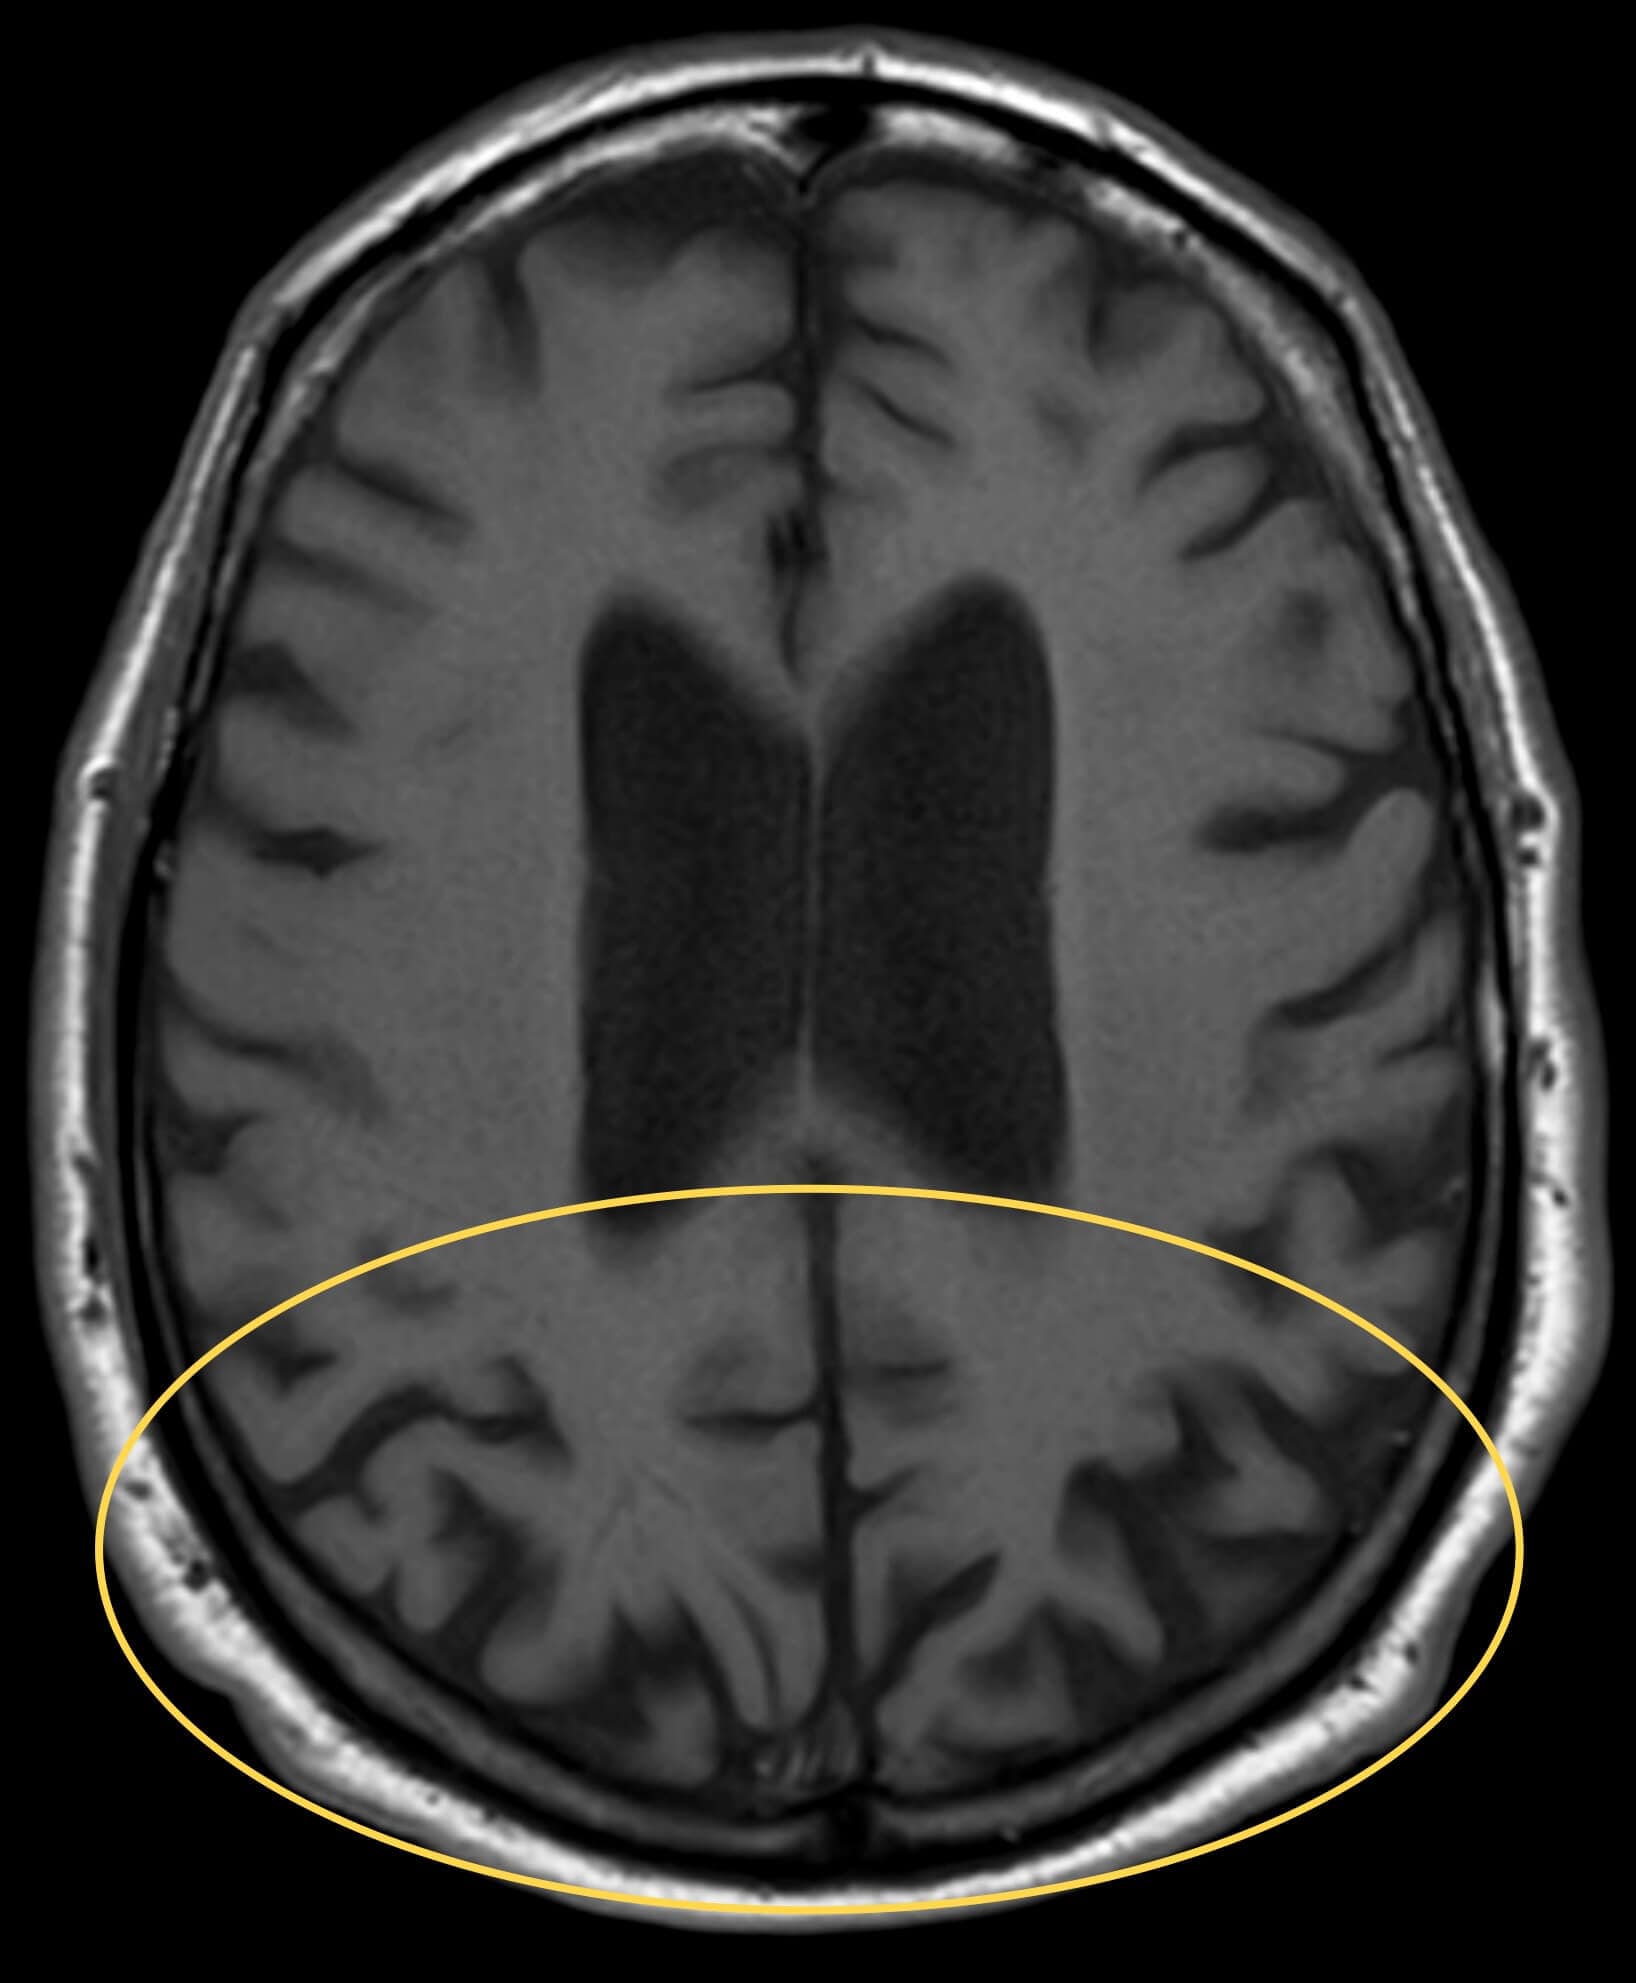

A neuropsychology evaluation was performed ten days after the initial encounter. The report stated the patient had stopped driving over two years prior due to “vision issues.” Given the age of onset and timeline of visual symptoms starting prior to memory loss, this evaluation suggested a diagnosis of PCA. The PCP later diagnosed Alzheimer’s disease, dementia, and prescribed memantine. It is speculated that the diagnosis of AD was made to address the memory loss for which the PCP was following the patient prior to available MRI findings. An MRI performed one month later showed central cortical atrophy, more prominently in the parietal and occipital lobes (Figure 2) and was otherwise unremarkable.

Figure 2. Transverse T1-weighted brain MRI image shows bilateral cortical thinning and sulcal widening in the bilateral occipital and posterior parietal regions (yellow oval).

There is no consensus on how to diagnose PCA, however, physicians rely on advanced neuroimaging to rule out other etiologies (e.g. stroke or tumor), along with the commonly found characteristics of PCA. Brain MRI can detect atrophy which predominantly affects the occipital, parietal, and posterior temporal lobes in PCA compared to the more diffuse cortical atrophy as observed in typical AD.2,3,18 Functional neuroimaging, such as single photon emission computed tomography (SPECT) and fluorodeoxyglucose positron fludeoxyglucose positron emission tomography (FDG-PET), may depict hypoperfusion and hypometabolism, respectively, of the occipito-parietal cortices.18,21